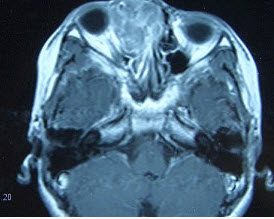

女,16岁,鼻塞、流涕一年余,失去嗅觉,影像检查如图所示,最可能的诊断是()。

A、鼻腔乳头状瘤

B、筛窦癌

C、恶性淋巴瘤

D、小唾液腺癌

E、嗅神经母细胞瘤

E